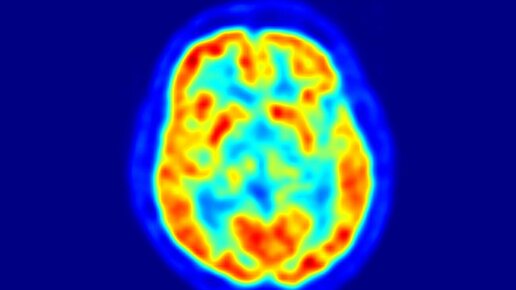

Нейронауки для всех. Методы: позитронно-эмиссионная томография

Медицина знает немало случаев, когда у внешне здоровых людей обнаруживались запущенные злокачественные новообразования либо с затрагиванием множества регионарных лимфоузлов, либо и вовсе с метастазами в другие системы органов. При этом людей ранее даже могли обследовать, делая рентген или проводя КТ. Очень точно опухоли мозга – например, глиомы – видит МРТ. Но иногда для того, чтобы найти опухолевый процесс на ранней стадии развития, бывает недостаточно даже сверхточных «фотографий» внутренних органов...